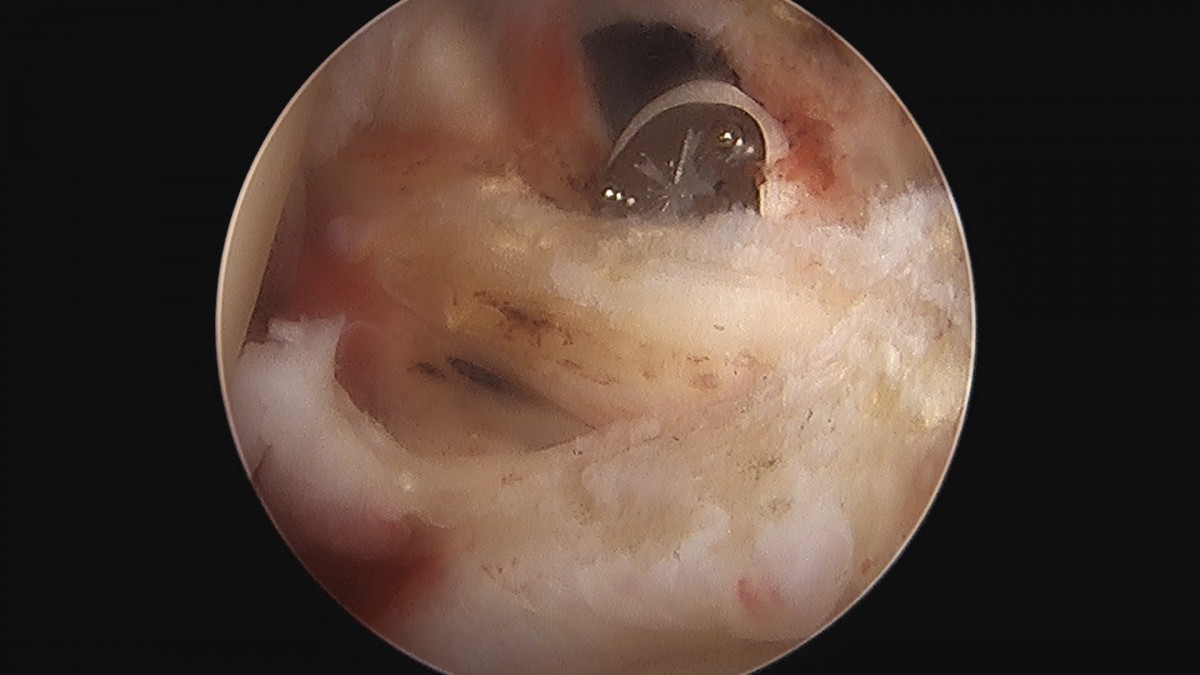

이재상원장님 어깨 견봉하 감압술 김봉O 환자

작성자 최고관리자 댓글 0건 조회 811회 작성일 25-09-16 15:28